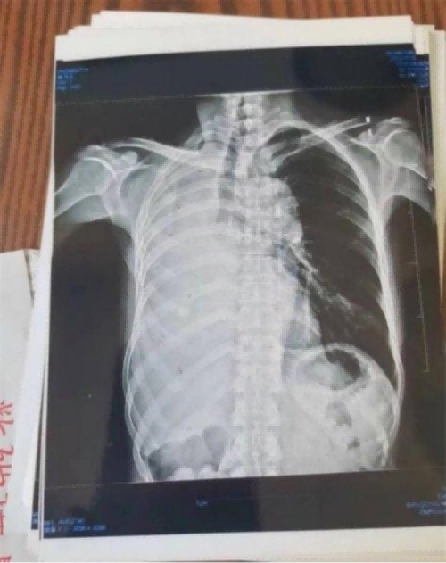

案例5右肺上叶癌(左侧颈部淋巴结转移、鳞状细胞癌)

患者岂六荣,53岁,系山西省晋中市左权县石匣乡管头村,于2013年1月9日前来就诊。因左胸憋闷,右肺呼吸困难,后背呈放射性疼痛近日加重。于2012年8月7日就诊于山西医科大学第一附属医院,行胸部CT示:右肺上叶癌,行气管镜示;右上叶后段支气管肺癌,右上叶支气管与右中间支气管分膌,右中间支气管开嗳累,病理回报:鳞状细胞癌(病理号12-12929)。于8月30日就诊于山西省肿瘤医院接受治疗。经该院各项检查最后诊断:右上叶癌: 左侧颈部淋巴结转移,鳞状细胞癌,化疗后出院于2012年9月19日转山西武警总医院(第一次入院),2012年9月19日。住院期间经过完善的相关检查,期间出现血小板低下,给予升血小板治疗后,血小板恢复正常,后行伽玛刀治疗后,同时给予中药抗肿瘤药今患者及家属要求出院,于2012年10月10日家属要求出院,住院21天。出院诊断;1、右肺上叶癌2、左侧颈部淋巴结转移3、血小板低下,白细胞低下4、乙型肝类(恢复期)。第二次住院(2012年11月9日)出院(2012年11月21日)共住院12天。今患者及家属要求出院,于今日自动出院。

于2o13年1月8日一2o13年5月28日纯中药临床治愈,14o天清零。停药一年半后做医学鉴定:未见肿瘤细胞。至今11年未見复发,未見转移,不服药。一直从事农业劳动。于2024年2月10日(春节)上午10点接通岂六荣电话时,他正赶着羊群往后山上的路上,当我问到中午吃饭怎样解决时:因后山上离村有六七里山路,只有随干粮充饥,并告诉我每天上午10点准时出犮,下午4点半就回到家了。当我问到他身体时:"自从在您那里治好后十一年至今天,不复发,不服药。我很好,很健康,请陈大夫放心”。今天是过大年,你们早点回去,给您拜年,祝您全家新年快乐,平安,幸福!

岂六荣的癌症通过陈老师的高超技艺彻底治愈,前几天陈老师跟他通话他还在山上放羊,山上的温度很低大约在零下二十多度,在山上放羊,追逐羊群,没有好的身体根本不行。现在岂六荣的身体状态特别好,甚至比之前的身体还好。这就是中医药的魅力所在,伟大之处。